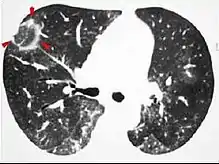

CT image showing ground-glass nodule (circled). CT image showing ground-glass nodule (circled).

Pre-malignant or malignant causes of nodular GGOs include adenocarcinoma, adenocarcinoma in situ, and atypical adenomatous hyperplasia (AAH). One large review study found that 80% of nodular GGOs which were present on repeated CT imaging represented either pre-malignant or malignant growths. Differentiating between pre-malignancy and malignancy on the basis of CT alone can pose a challenge to radiologists; however, there are several features that that are indicative of pre-malignant nodules. AAH is a pre-malignant cause of nodular GGO and is more commonly associated with lower attenuation on CT and smaller nodule size (<10 mm) compared to adenocarcinoma.[11] In addition, AAH often lacks the solid features and spiculated appearance that are often associated with malignant growths.[10] In contrast, as adenocarcinoma becomes invasive it will more often cause retraction of adjacent pleura and may show an increase in vascular markings. Nodules >15 mm almost always represent an invasive adenocarcinoma.[10][11]

There are numerous potential causes of nodular GGOs which can be broadly separated into benign and malignant conditions. Benign conditions potentially leading to the formation of nodular GGOs include aspergillosis, acute eosinophilic pneumonia, focal interstitial fibrosis, granulomatosis with polyangiitis, IgA vasculitis, organizing pneumonia, pulmonary contusion, pulmonary cryptococcus, and thoracic endometriosis. Focal interstitial fibrosis presents a unique challenge when differentiating from malignant nodular GGOs on CT imaging. It is typically persistent over long-term imaging follow-up and shares a similar appearance to malignant nodular GGOs.[10]